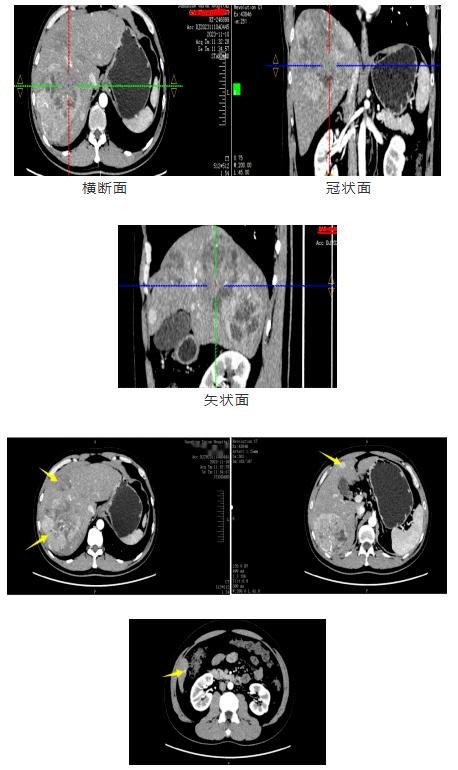

影像资料

诊断:肝恶性肿瘤(CNLCIIb)乙型肝炎肝硬化。